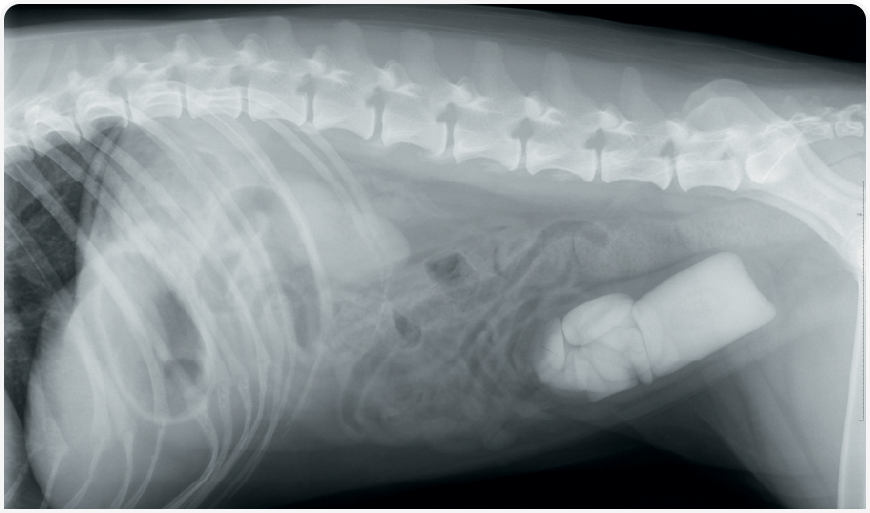

Классификация, диагностика и терапия инфекций мочевыводящих путей у собак